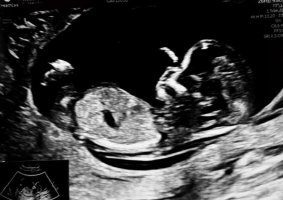

Takk for all omtanke! Perfekt liten skatt som vinka til oss, og medtatt mamma etter operasjon/innleggelse av hickman. Smertepåvirka no, men vel overstått. Og viktigast av alt, at baby ser tilsynelatande frisk ut! Då står eg faktisk i alt, både smerte og evig oppkast